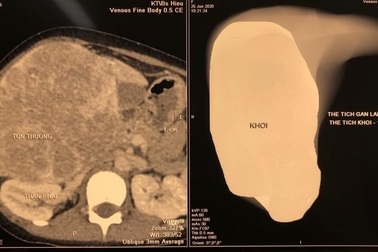

Trẻ mới 12 tuổi đã mắc ung thư gan, cha mẹ cần cảnh giácBệnh nhi nhập viện vì bụng to bất thường, khối u gan to chiếm gần hết vùng bụng. Theo bác sĩ trẻ mắc u nguyên bào gan, một dạng ung thư gan.